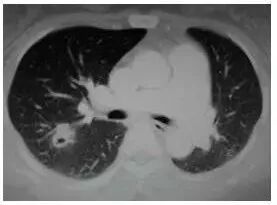

在初期(< 1 cm)往往很纯、密度很低、边界也清晰,这时还不一定是恶性的,可以称为「纯 GGO」。

切除后多证实为腺瘤样不典型增生(AAH,癌前病变)或原位腺癌(AIS,未侵犯周围血管间质、不会转移,5 年生存率 100%),极端情况下也可是微浸润腺癌(MIA,侵犯周围血管间质 < 5 mm,不会转移,切除后 5 年生存率 100%)。